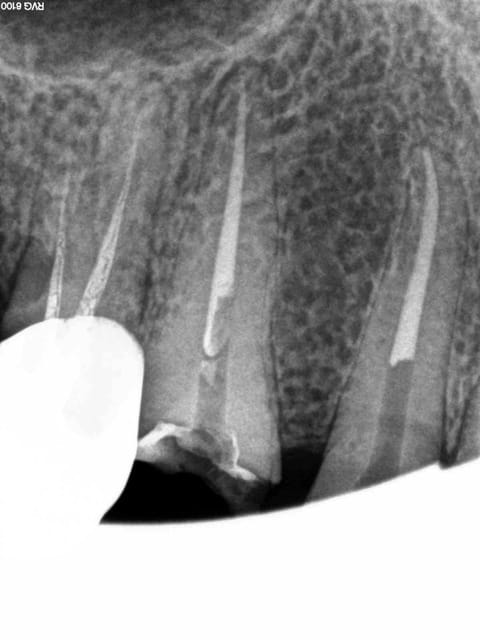

Gutta scellée au tubuli seal avec ou sans condensation thermo mécanique.

Logement du tenon réalisé au friendo ( voir photos) qui fond la gutta ( 200 ° au niveau de l'insert) . Un coup de machtou et hop tu peux passer les forets.

Avantage tu peux faire les provisoires et l'empreinte dans la séance et surtout tu peux raser les couronnes ce qui est un réel plus pour les endos surtout avec des pulpes rétractées comme ici ca évite de faire des conneries avec un abord palatin ou on ne voit rien du tout.